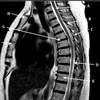

1

Q

What is letter A?

A

4TH VENTRICLE

What is letter B?

CEREBELLUM

3

What is letter C?

POSTERIOR ARCH OF C1

4

What is letter D?

5

What is letter E?

CSF

How well did you know this?

Not at all

2